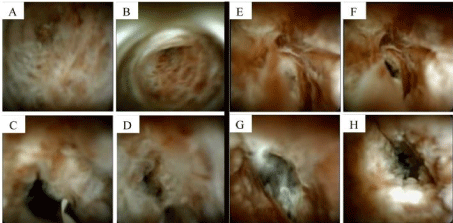

An ERCP found diffusely dilated ducts. The CBD had a severe stenosis 15 mm length and brushings were obtained. SOPOC revealed frond-like, nodular mucosa with increased vascularity concerning for malignancy, Figure 2. Unfortunately, targeted biopsies were not taken during the procedure due to lack of instruments.

Figure 2. Comparison of CCA (images A-D) and EC (images E-H). Note that they are indistinguishable from each other on SOPOC.

SOPOC allows direct visualization and improvement in image quality, single-operator use, and the capability to perform targeted biopsies allowed SOPOC to become a powerful tool in diagnostic challenges of biliary strictures. A meta-analysis showed pooled sensitivity of 66.2% and specificity of 97.0% in diagnosis of malignant stricture [13]. Another randomized trial demonstrated the overall accuracy of targeted biopsy of SOPOC was superior (87.1%) compared to standard brushing or biopsy sampling (65.5%) [14]. The visual inspection alone from SOPOC can differentiate malignant from benign stricture with reasonable accuracy (97.2%) [15]. However, the SOPOC images of our patient illustrates EC can have features to suggest malignant stricture such as frond-like nodular mucosa, luminal narrowing, and increased vascularity. Comparison of our patient with EC to another patient with cholangiocarcinoma are shown in Figure 2. Their images are indistinguishable.